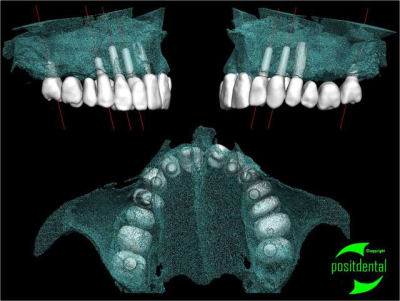

Avulsion, implantation, mise en charge immédiate en 1 temps chirurgical avec provisoire à armature métal.

Je n'ai eu que le scan du haut pour faire la S.I.A.O.

je préfères ton évolution dans la répartition des implants, 8 c'est bien!

> je préfères ton évolution dans la répartition des implants, 8 c'est bien!

je dirais 6, car les 2 du fond, j'aime pas trop, mais peut-être que c'est juste moi qui les trouve petits...

nouveau ML 47 L 7mm EASYIMPLANT

leur fonction est uniquement éviter le porte-à-faux d' une extension